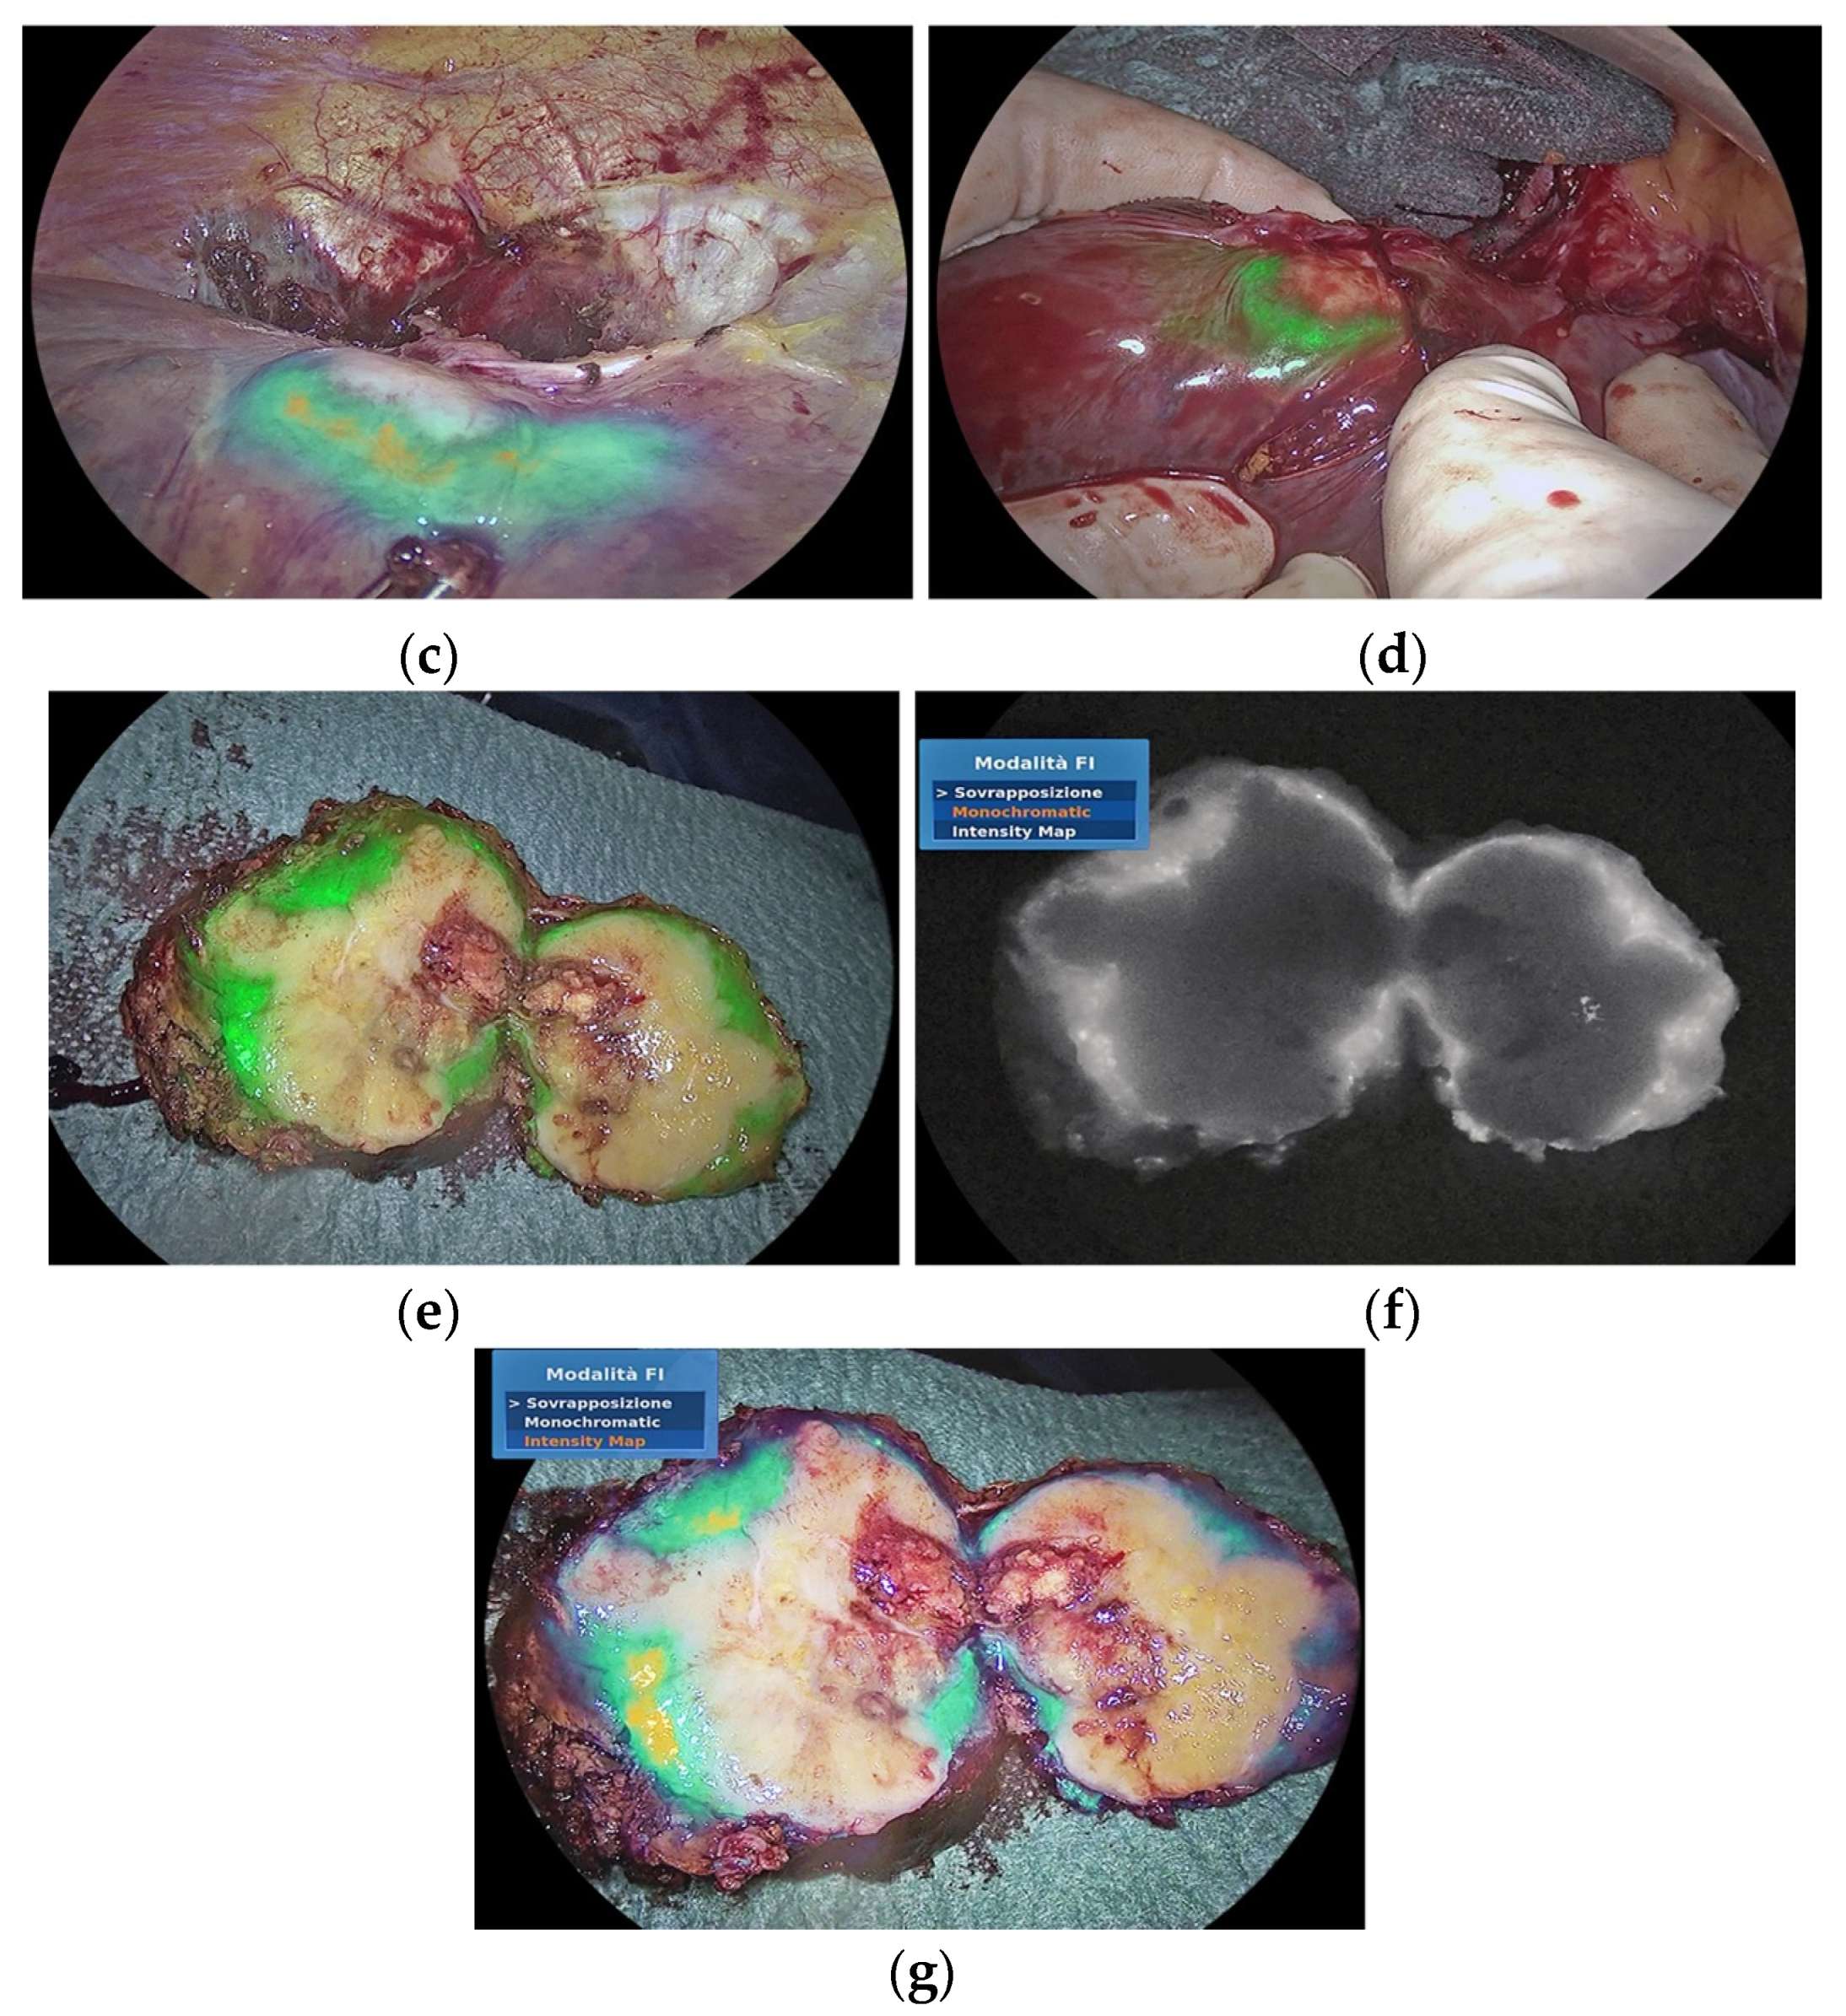

3.2. Improving the Detection of Cancer Tissue and Targeted Treatment

- Raimondo, D.; Maletta, M.; Malzoni, M.; Cosentino, F.; Scambia, G.; Falcone, F.; Coppola, M.; Turco, L.C.; Borghese, G.; Raffone, A.; et al. Indocyanine green fluorescence angiography after full-thickness bowel resection for rectosigmoid endometriosis: A multicentric experience with quantitative analysis. Int. J. Gynecol. Obstet. 2021, 158, 679–688. [Google Scholar] [CrossRef]

- González-Abós, C.; Selva, A.B.; de Lacy, F.B.; Valverde, S.; Almenara, R.; Lacy, A.M. Quantitative Indocyanine Green Fluorescence Imaging Assessment for Nonmucinous Peritoneal Metastases: Preliminary Results of the ICCP Study. Dis. Colon Rectum 2021, 65, 314–321. [Google Scholar] [CrossRef] [PubMed]